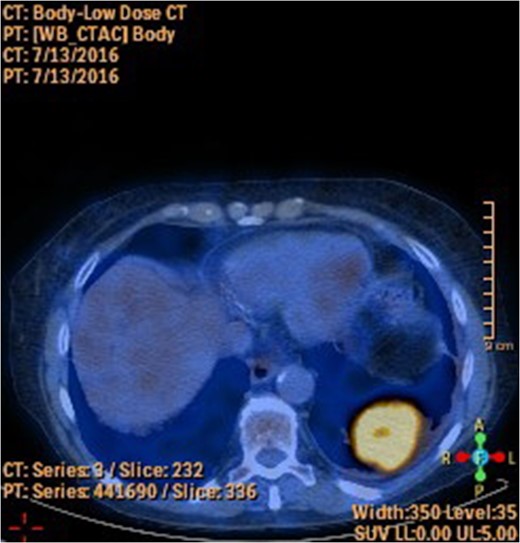

A 78-year-old female presented with worsening abdominal pain over 1 week, with onset of symptoms occurring 3 months prior. No history of recurrent fever or weight loss was elicited. There were no changes in bowel habits and she denied melena or hematochezia. She endorsed a normal colonoscopy three years prior. Of note, she was diagnosed with a biopsy proven squamous cell cancer of her left lower lobe 4 months earlier (Fig. 1). A PET scan performed just three weeks prior to her presentation demonstrated significant FDG uptake in the left lower lobe as well as the cecum, with no convincing evidence of regional nodal disease in the lungs (Figs 2 and 3).

The importance of establishing the right diagnosis is exemplified in our case. Our patient was referred to a thoracic surgeon for consideration of oncologic resection of her primary lesion. While the presence of a colonic primary certainly influences the decision regarding management, the presence of metastatic disease to the GI tract negates curative resection and portends a poor prognosis. Of note, our patient demonstrated isolated colonic metastasis in the absence of regional nodal disease on PET-CT. The sensitivity of PET-CT in detecting mediastinal disease has been shown to be as low as 78%, likely influenced by a multitude of factors including tumor biology [6]. As such, an area of distant FDG-avid activity should be presumed to represent metastatic disease, even in the absence of regional or mediastinal disease, until proven otherwise.